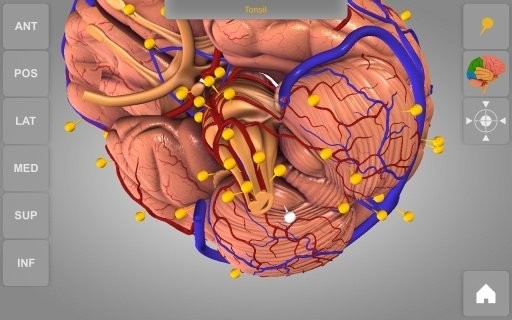

3D脑部解剖app是一个技术专业医药学解剖软件,软件给予脑部的神经组织和有关所有材料,客户还可以根据实际的仿真模拟自然环境,来提升自身的认知能力,来提升自己的临床水准。

3d脑部解剖是真正详细的三维学习培训身体解剖学运用,具备三维部位监测和视频语音发音,根据领先的互动式三维触碰页面。

您还可以将实体模型转动到随意视角并扩大和变小

虚似解剖:剥掉全身肌肉层以展现其下边的解剖结构

1、详尽的3D身体解剖实体模型

2、高像素画面质量,更强的视觉盛宴

3、解剖结构附带对应的文字描述